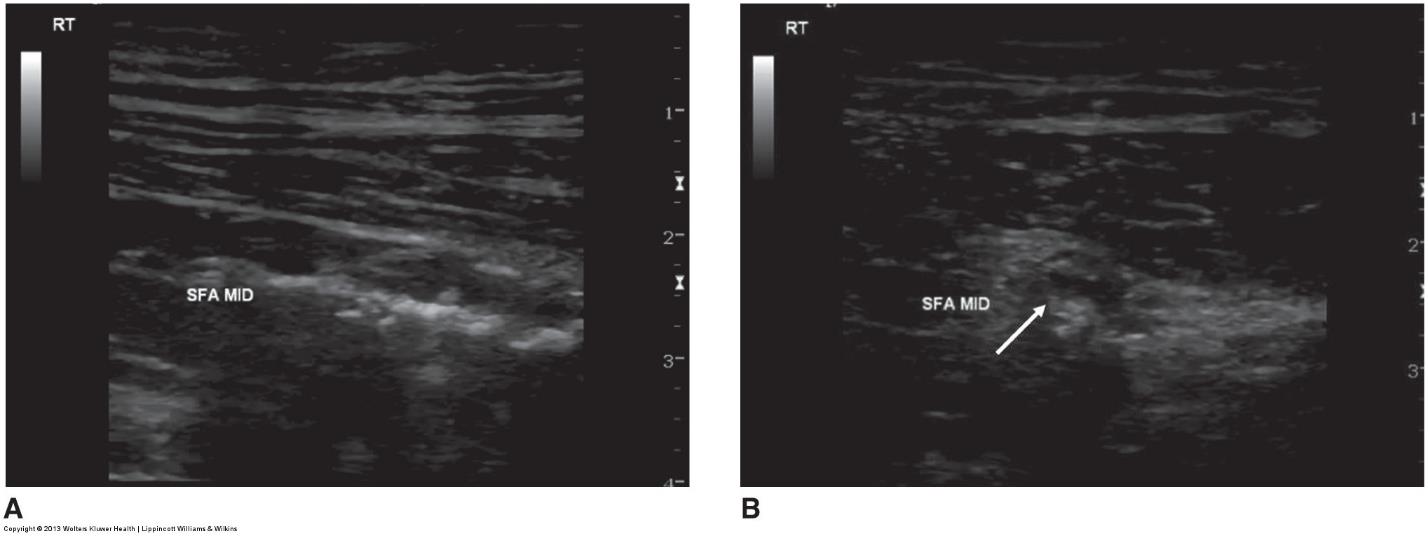

an ultrasound image of an artery w/ atherosclerotic plaque

what does image A represent

what does image B represent